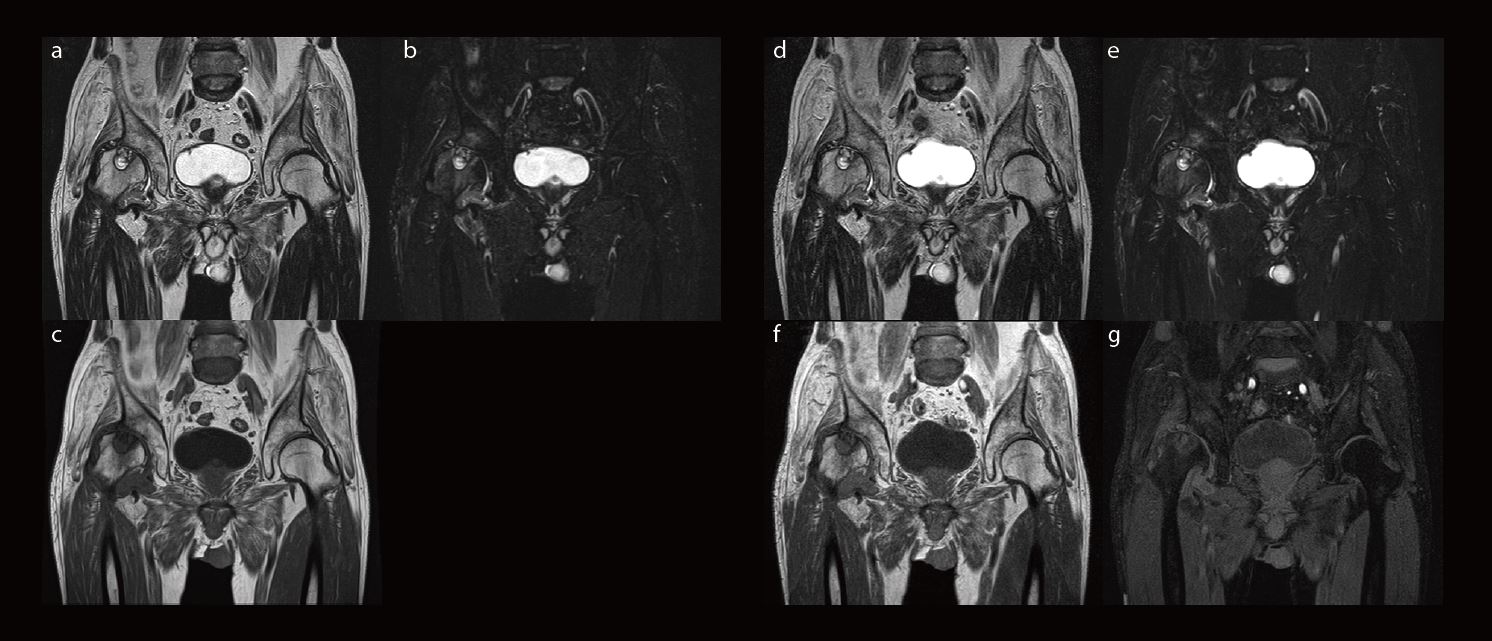

На рис. 2 наведено клінічний випадок остеоартрозу кульшового суглоба. Замість виконання трьох окремих сканувань для отримання трьох типів зображень (T2-зважених, STIR і T1-зважених зображень) було виконано два сканування за допомогою WFS DIXON для отримання чотирьох типів зображень. Чітко видно кісту правого кульшового суглобу завдяки відмінному співвідношенню сигнал/шум.

Рис.2. Ліворуч: зображення, отримані традиційним методом. (a) T2WI, (b) T2WI STIR, (c) T1WI. Праворуч: зображення, отримані за допомогою WFS DIXON. (Верхній ряд: T2WI WFS DIXON, нижній ряд: T1WI WFS DIXON) (d), (f): зображення у фазі, (e), (g): зображення води. Час сканування становив приблизно 5 хвилин для обох методів, але WFS DIXON надає чотири типи зображень, тоді як звичайний метод надає лише три типи зображень.